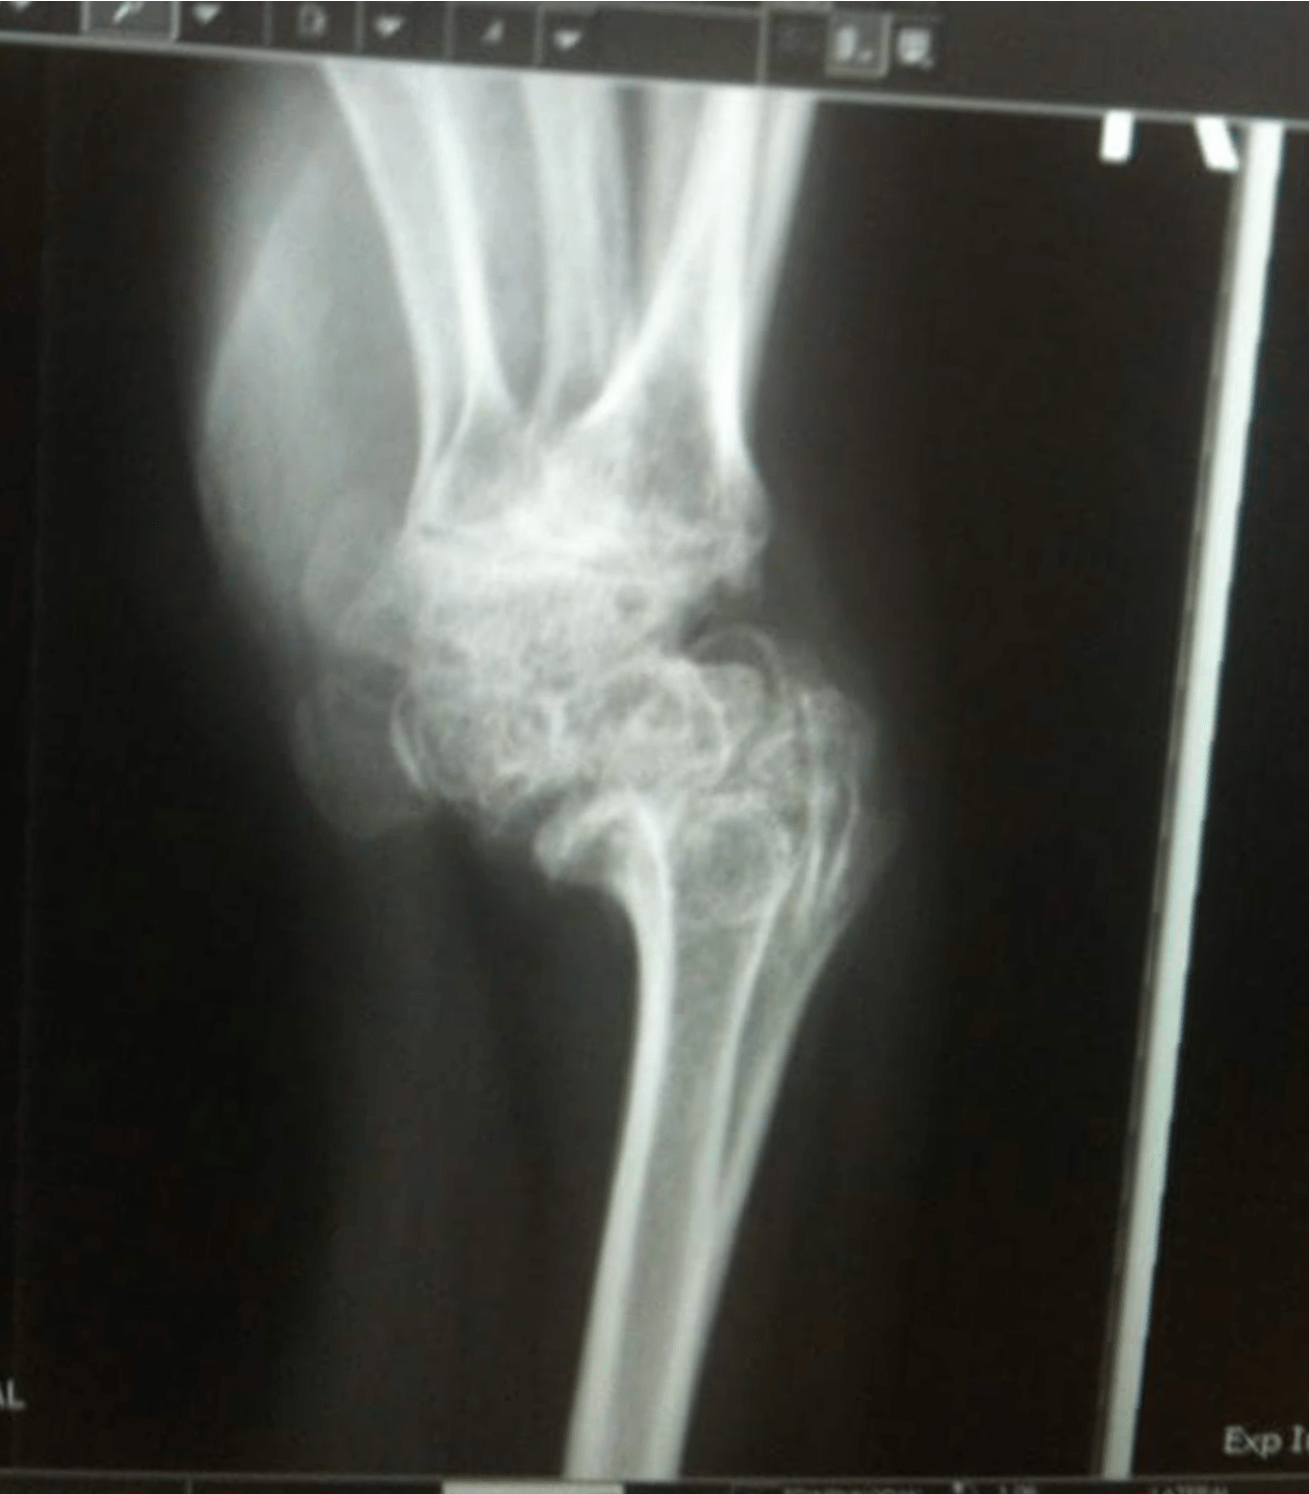

From www.reddit.com

Psoriatic arthritis ate my wrist joints & 3 carpal bones (Part 2 Ortho Or Radiology Unless you do ir, your radiation exposure will likely be higher in ortho than in diagnostic radiology due to use of intra op fluoro. Radiological imaging is an essential modality for investigating patients with musculoskeletal conditions, including trauma. Based on our study, orthopaedic providers are significantly faster, more accurate, and make fewer mistakes affecting patient care while. So far i've. Ortho Or Radiology.